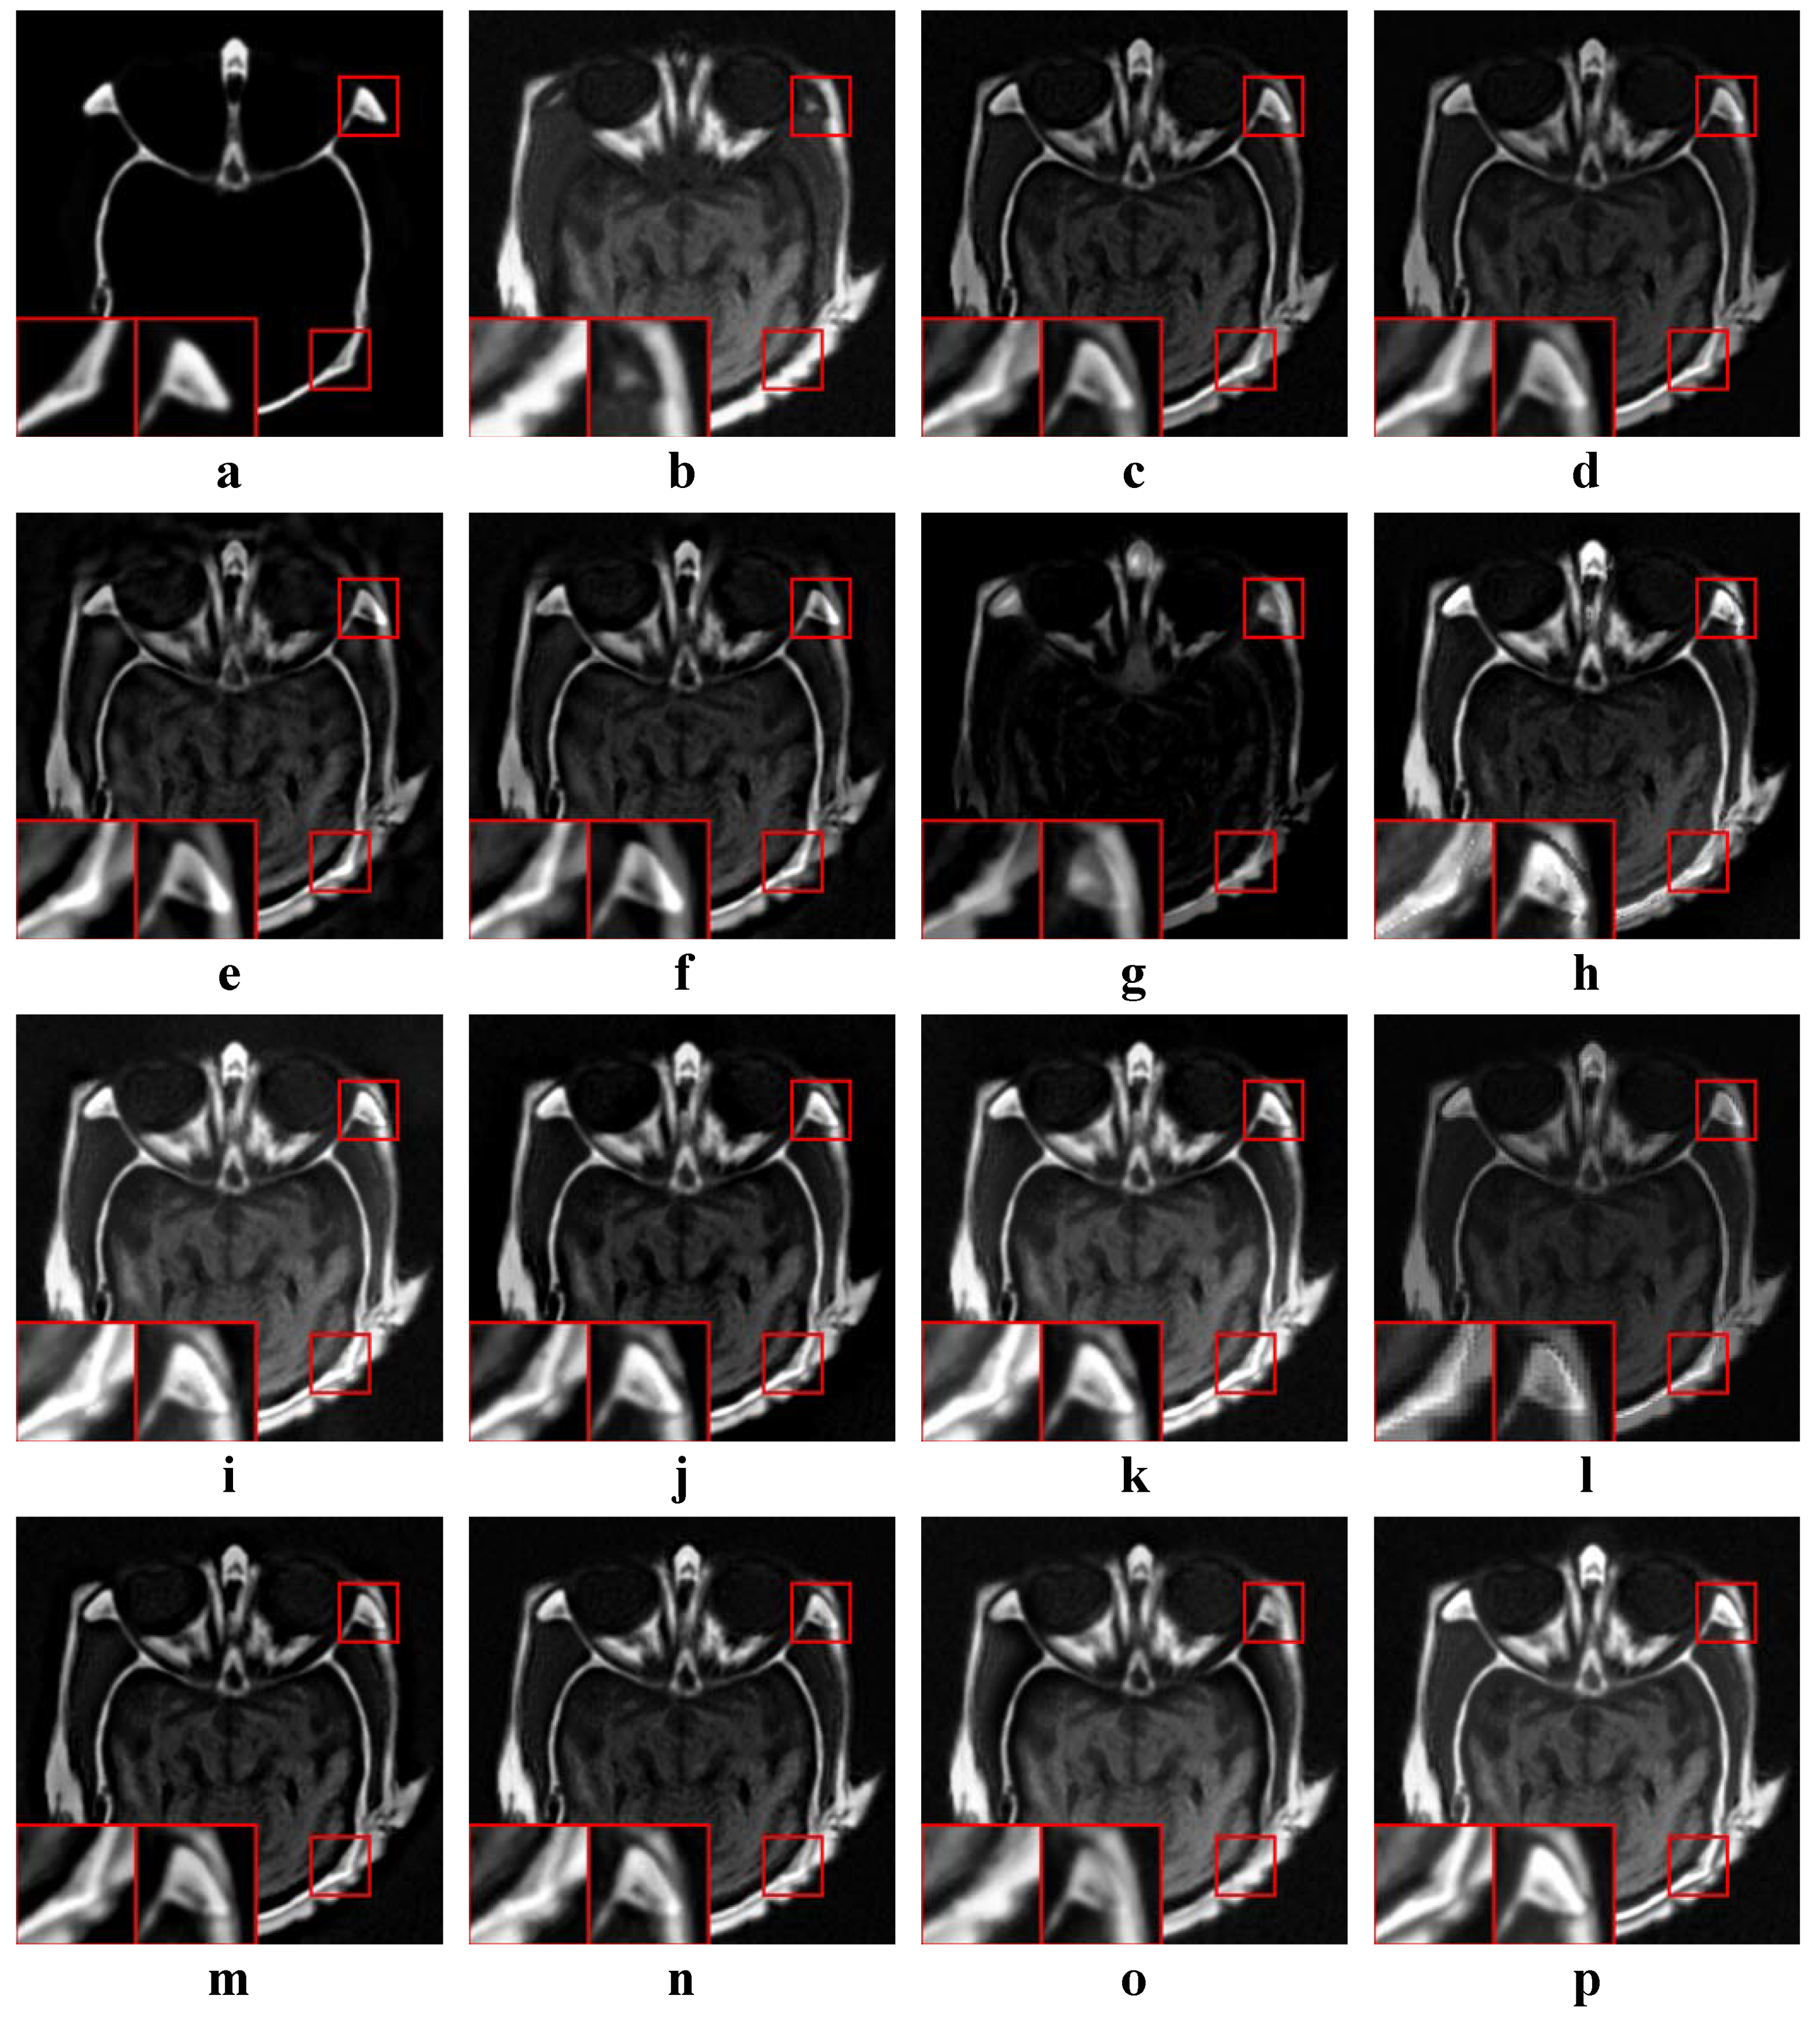

In this experiment, all four categories of source images were tested. The average values of the objective metrics of each category were compared separately. Some examples of the fused images are shown in Figure 10, Figure 11, Figure 12 and Figure 13. The average values of the objective metrics are shown in Table 5, Table 6, Table 7 and Table 8.

4.4.2. Analysis of Medical Results

According to Figure 11, our method produces both high contrast and clear structures. With the exception of CNN, MSSR, FFIF and our method, all other methods make the texture from the middle part of (b) unclear due to low contrast. However, the structures produced by CNN, MSSR and FFIF are not as clear as our method.

According to Table 6, our method is the best on Q A B / F and the second best on M I and N C I E . FFIF is the best on M I , F M I and N C I E , while it is the second best on Q A B / F . ASR is the second best on F M I . However, the edges and structure of the FFIF result are unclear. The structures of the two source images are mixed together, and it looks confusing. The result of ASR has low contrast and the middle part of the fused image is not clear. As pointed out by Q A B / F , our method has the best visual quality. At the same time, our method also has high information entropy.

Figure 11. Examples of the fusion results of medical images. (a,b) Source images; (cp) The fused results of ASR, CSR, CVT, DTCWT, GTF, H-MSD, CNN, LP, MSSR, MSVD, NSCT, WLS, FFIF, and our proposed method, respectively.